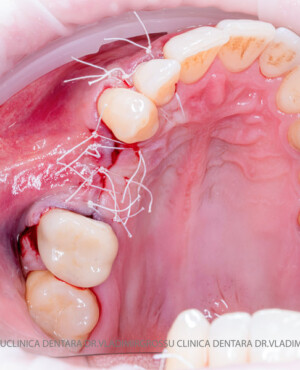

Aditia gingivală este o procedură chirurgicală ce corectează diverse probleme estetice și funcționale, cum ar fi recesiunea gingivală. În implantologia modernă, aditia de țesut moale este utilizată aproape în fiecare intervenție de inserție a implantului dentar pentru a asigura un aspect estetic natural și o bună integrare a implantului în cavitatea bucală.

Adiția osoasă are un rol crucial pentru poziționarea corectă și stabilă a implanturilor dentare. Clinica stomatologică Dr. Grossu din Chișinău promovează o abordare chirurgicală estetică și predictibilă, adaptată fiecărui caz în parte.

Un element esențial în procedura de aditie osoasă este utilizarea membranelor biologice, care izolează materialul osos de țesuturile moi (gingie) pe durata procesului de vindecare. Cele mai recomandate sunt membranele resorbabile din colagen sau pericard.